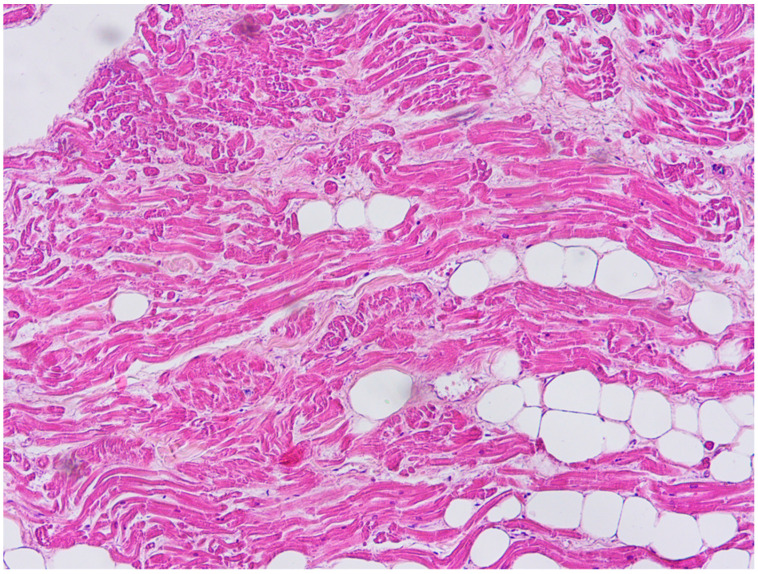

A 20-year-old young man (body mass index: 28) suddenly died in a public place. The friend who witnessed his death declared that he had recently smoked cannabis. All the witnesses said that the young man appeared in good health and that he suddenly collapsed (without any previous symptom). Basic life support maneuvers were promptly started, but when paramedics arrived, he was asystolic at ECG. The public prosecutor requested an autopsy to find the cause of the death. The victim played several competitive sports and had a syncope while playing football three years before. At external examination of the body no relevant sign was found. At the autopsy, performed five days after the death, the heart was isolated and fixated in toto in a 10% buffered formalin-based solution (Figure 1 and Figure 2). Both the lungs appeared swollen (weights: left—450 g, right—940 g), and multiorgan congestion was observed. Heart examination (weight: 530 g, longitudinal diameter: 11 cm, transverse diameter: 13 cm) presented no anomaly. Atria, valves, left ventricle (anterior wall thickness: 1.3 cm; lateral wall thickness: 1.4 cm; posterior wall thickness: 1.7 cm; interventricular septum thickness: 1.5 cm) and right ventricle (wall thickness: 0.5 cm) did not show any macroscopic relevant finding. Coronary circulation was right dominant. Left anterior descending coronary artery presented, at 2 cm from its beginning, a 0.3-cm-thick 5.5-cm-long myocardial bridging (Figure 3). Other coronary arteries were macroscopically normal. The conduction system was carefully analyzed, and serial sectioning targeted blocks of areas of interest [ref. 12,ref. 13]. Histopathological examination of the myocardium (Figure 4) found wavering of myocardial fibers, fibrosis and disarray in the left ventricle myocardial area above the MB (Figure 5); fibrosis in sino-atrial node area (Figure 6) and infiltration of fatty tissue (separated the myocardium) in the antero-lateral region of right ventricle free wall (Figure 7). The atrio-ventricular node presented no microscopic anomalies. No signs of myocarditis were found.

In our case, there also was a sign suggestive of arrhythmogenic cardiomyopathy (ACM): the fatty infiltration of the right ventricle. However, this feature was only found in the antero-lateral region of the right ventricle, a localization that is typical of physiological conditions [ref. 38]. Moreover, the fatty infiltration was clearly separated by the myocardium, and there were no signs of necrosis/atrophy of the myocytes (that are typical of ACM), no fibrous or fibro-fatty infiltration of the myocardium (common among young cases of ACM) and no inflammatory infiltrates (that can be present, for example, in ACM hot phases, i.e., the phases of acute myocarditis that can suddenly complicate the disease) [ref. 37,ref. 39]. Finally, NGS found no variant pathogenic for ACM. All these data suggest a physiological condition. However, this finding is atypical, because fatty infiltration of the myocardium generally affects elderly or obese patients, and our case was young and non-obese (albeit overweight). Hence, since the absence of signs of cardiomyopathy, a clear pathogenic significance cannot be given to the findings. However, it should be considered that some authors reported that fatty infiltration could cause arrhythmias because it represents a structural barrier to the heart electrical impulse and causes oxidative stress. In particular, previous cases of sudden death in patients with fat of the free wall of the right ventricle have been reported [ref. 40].